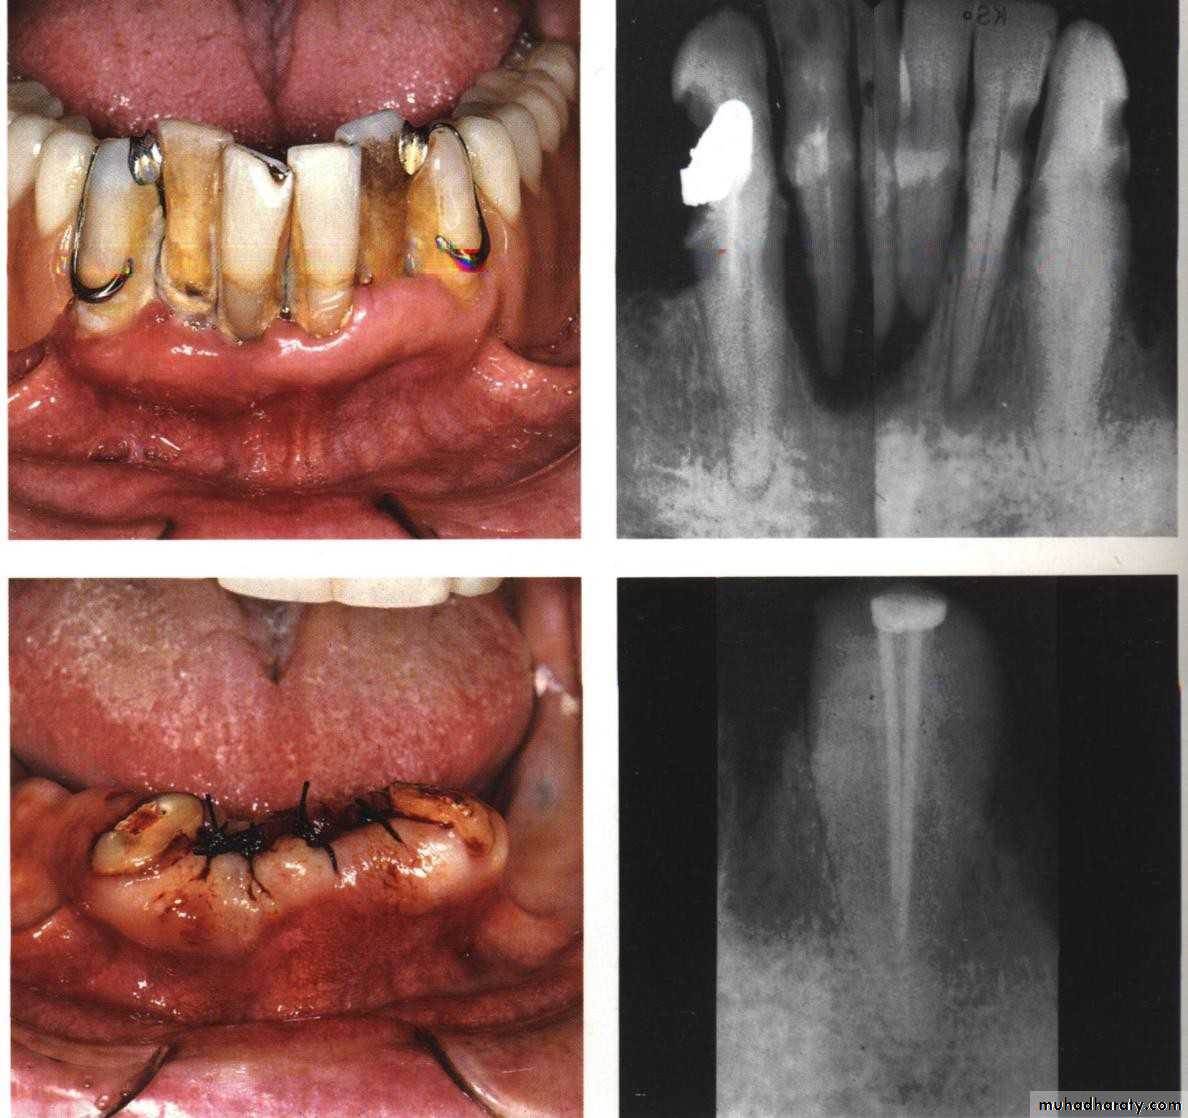

• 1) Immediate overdenture.

• Immediate Overdenture

• It’s constructed prior to the preparation of abutment teeth and inserted after the preparation.

• When the processed denture is fitted, it is relined with cold cured acrylic in the areas around the abutment teeth to make it fit as well as possible.

• 5) Submerged root:

• Abutment reduced to level below gingival margin, so need extra retentive attachment (intracoronally).• RCF .... if needed

• If planned…